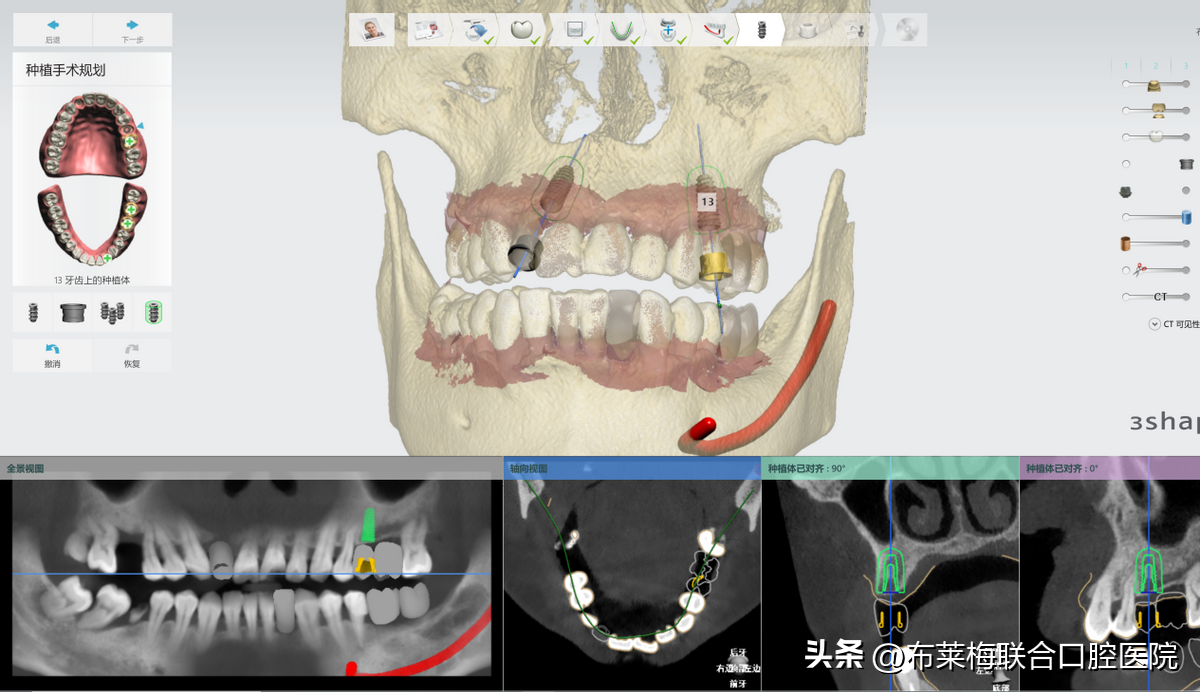

數(shù)字化種植牙技術(shù)可以讓醫(yī)生提前設(shè)計(jì)出調(diào)節(jié)方案,再在計(jì)算機(jī)上模擬生成術(shù)后果圖供患者和家屬確認(rèn)。

真真實(shí)實(shí)的在大屏幕上看到自己的方案,以及種植操作時(shí)的過程,植體走哪里安進(jìn)去,有沒有避開神經(jīng),都是一清二楚。不僅放患者安心,更讓陪同的家屬放心

數(shù)字化種植牙技術(shù)簡單來說,就是手術(shù)中提前預(yù)判好術(shù)中可能會(huì)出現(xiàn)的風(fēng)險(xiǎn),同時(shí)把誤差減少到毫米,提前讓醫(yī)生和患者知悉確認(rèn)的。降低了手術(shù)的風(fēng)險(xiǎn)系數(shù),也可以讓患者稍微放松心情??謶质窃从谖粗菍⑦@些信息都提前告知患者和家屬,自然對手術(shù)也就不會(huì)過度緊張

數(shù)字化種植牙利用計(jì)算機(jī)計(jì)算出牙骨組織情況,準(zhǔn)確測量種牙的位置、角度、深度,做到量體裁衣